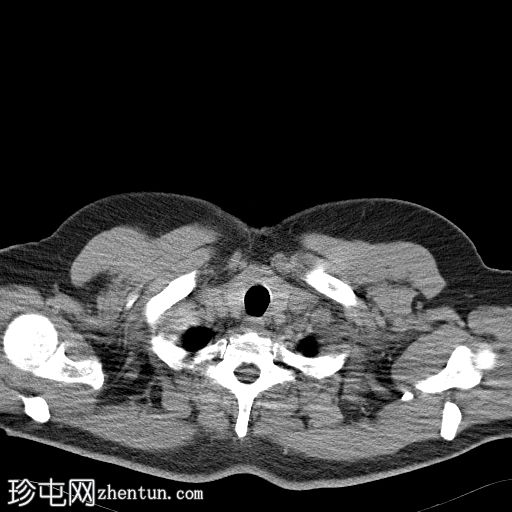

轴位平扫

盆腔内可见一大小为12 x 17 cm的边界清晰的异质性软组织肿块,向下延伸至下腹部。肿块内未见钙化或脂肪密度影。肿块向下推挤膀胱,并牵拉周围肠袢,但无放射学侵犯证据。未见明显淋巴结肿大、腹水或气腹。未见肺部或骨骼局灶性病变。肝脏可见数个小的单纯性囊肿。患者存在少量Bosniak I型肾囊肿,双侧肾盂肾盏系统饱满。曾行胆囊切除术。